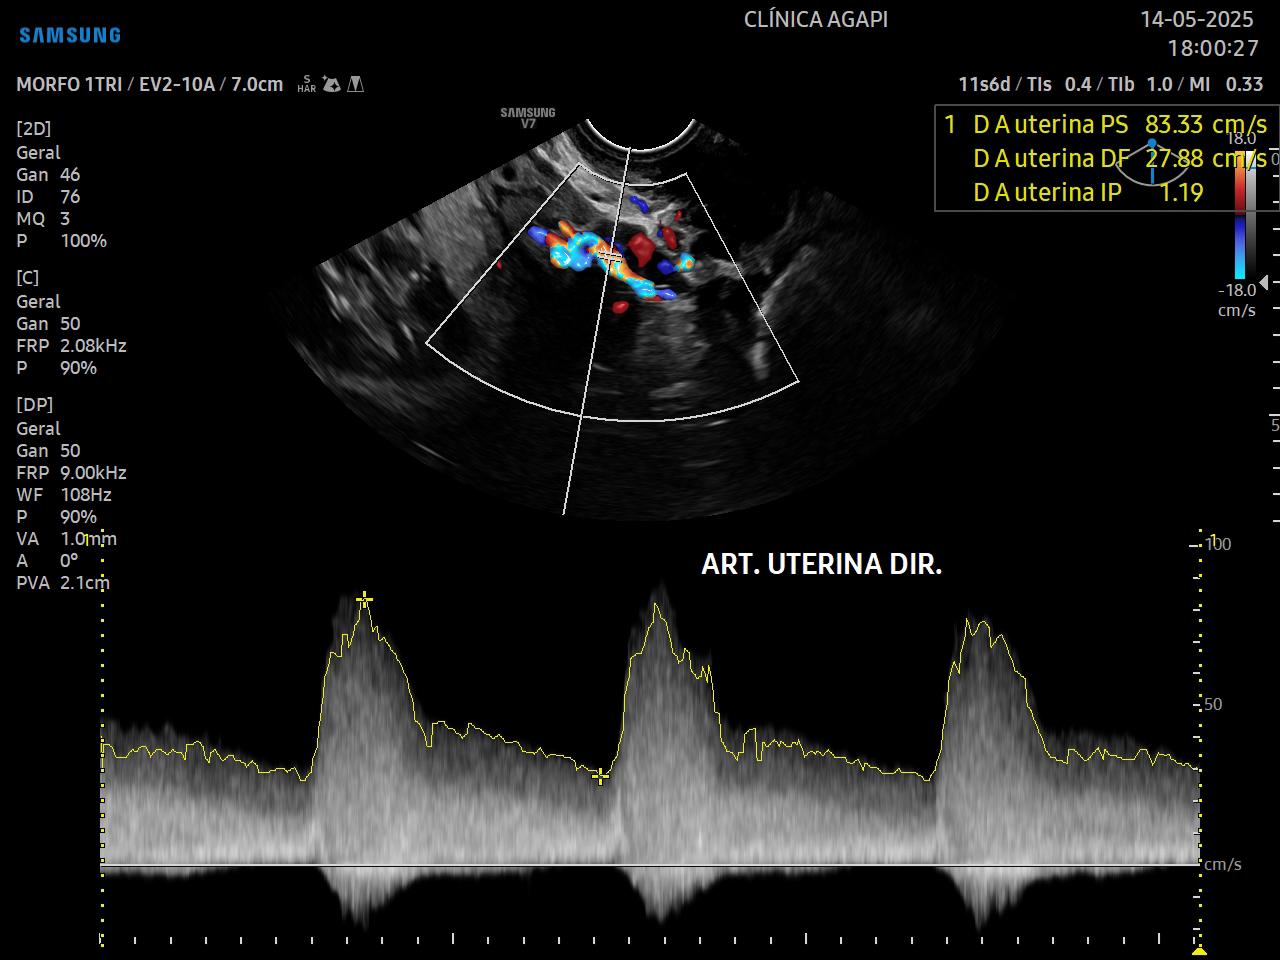

A rastreio de pré eclâmpsia é feito a partir da junção da história materna, pressão arterial média e doppler das artérias uterinas.